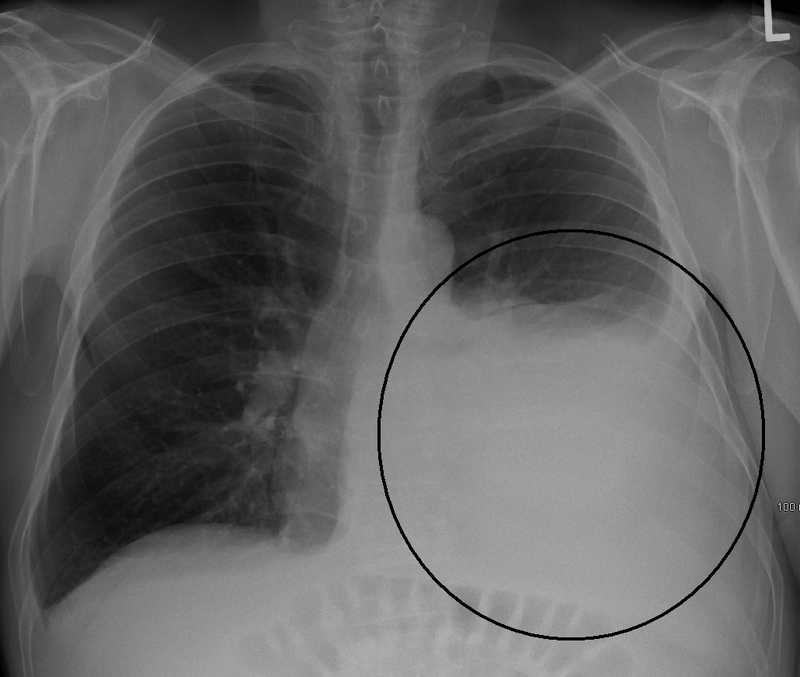

Sinh thiết màng phổi mù thường được chỉ định với những trường hợp người bệnh bị tràn dịch màng phổi tiết dịch hoặc dịch đỏ máu. Đây là tình trạng trong khoang màng phổi xuất hiện dịch nhiều hơn mức sinh lý bình thường. Tình trạng này chính là nguyên nhân làm biến đổi trên lâm sàng và X-quang. Tuy nhiên, sinh thiết màng phổi mù vẫn chống chỉ định với một số trường hợp sau đây:

Ngoài việc được giải thích về mục đích và các tai biến, người bệnh cần thực hiện một số xét nghiệm cần thiết như xét nghiệm công thức máu, xét nghiệm đông máu, siêu âm màng phổi, x-quang phổi, CT ngực.